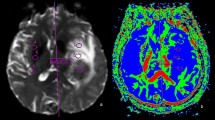

Graphical Abstract

A total of 135 metastatic lesions were identified in all subjects and considered as the true number of lesions (mean per subject 2.41, SD 6.4, range 0–46). Zero metastatic lesions were identified in 22 subjects, while > 1 metastases were detected in 16 subjects. Examples of metastases on SE and SPACES sequences at 1.5 T and 3 T are shown in Figs. 1, 2, 3, and 4. No significant difference in number of metastatic lesions reported at 1.5 T versus 3 T were detected (p = 0.79). Relatively fewer metastases were detected on the sequence temporally closer to contrast administration (irrespective of sequence type); however, the difference did not reach statistical significance at the pooled level (p = 0.08), nor at the level of individual raters (R1, p = 0.16; R2, p = 0.19; R3, p = 0.5).